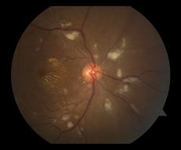

Fotografia do fundo do olho direito centralizado no nervo óptico, mostrando várias manchas algodonosas e exsudações maculares em uma configuração de estrela ao redor da fóvea

Cortesia de Angie Wen MD, residente, New York Eye and Ear Infirmary, Nova York; usado com permissão.